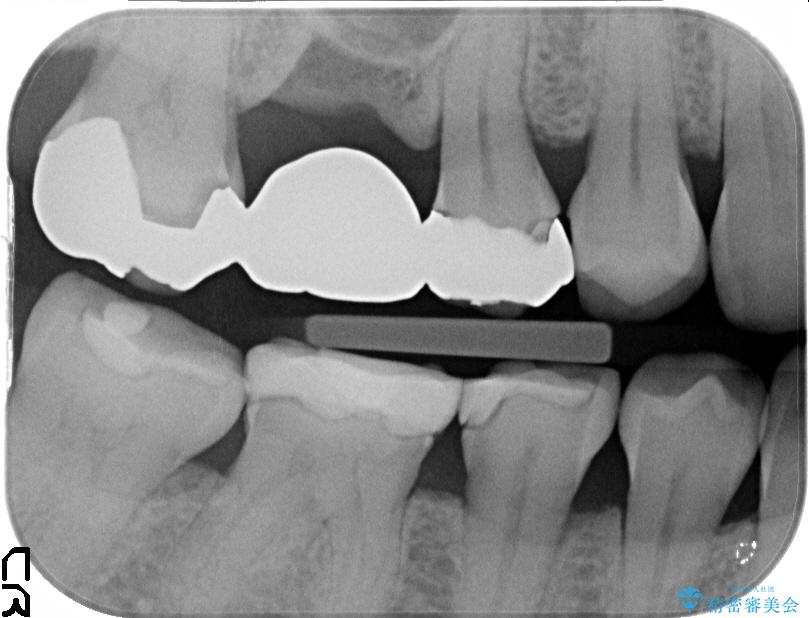

初診の際に撮影したレントゲンにて以前他院で治療していた詰め物が適合不良であることが判明し、再度治療をしてほしいとのご希望でした。

ぱっと見ただけでは特に問題ないように見えますが、レントゲンをよく確認すると詰め物と歯の間に隙間がはっきりと確認ができます。

隙間が発生しているインレー(詰め物)

治療完了した歯でも、時間の経過や力的作用によってセメントが変性したり、隙間が空くことによって詰め物の下に虫歯が発生したりすることがあります。